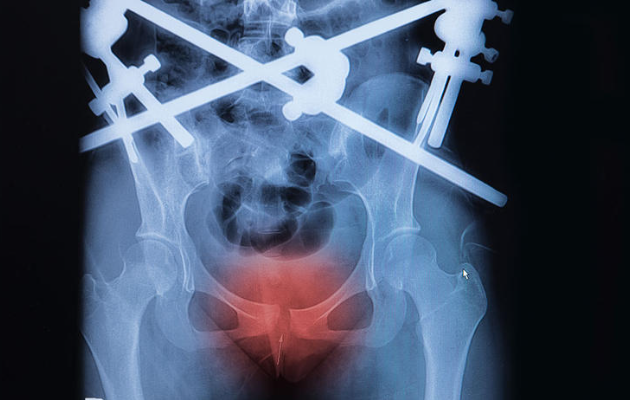

Gãy xương vùng chậu rất hiếm: chiếm chỉ 3% các trường hợp gãy xương, theo kết quả của Viện đào tạo phẫu thuật chỉnh hình Hoa Kỳ. Tuy nhiên trường hợp này có thể xảy ra. Ước tính có khoảng 8 đến 9% số ca chấn thương vật cùn – do ngã hoặc tai nạn giao thông – kết quả là chấn thương vùng chậu.

Tin tốt là phần lớn các ca gãy xương chiếm tối thiểu – và trong khi chúng thường đau dữ dội – nhưng lại ít khi cần phẫu thuật. Và đôi khi bạn chỉ đang quá sợ sau khi bị tai nạn, nên chụp Xquang để chắc chắn.